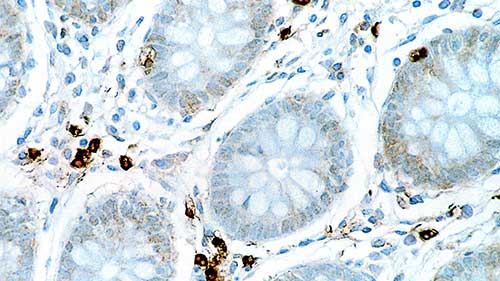

Human colon, ulcerative colitis: immunohistochemical staining for CD16. Note intense membrane staining of infiltrating natural killer cells, granulocytes and activated macrophages. CD16: clone 2H7

Das CD16-Antigen weist ein Molekulargewicht von 50 bis 70 kD auf. Es handelt sich um einen niedrig affinen Rezeptor für den Fc-Teil komplexierter IgG (Fc/gamma RIII), der auf natürlichen Killerzellen (NK-Zellen), Granulozyten, aktivierten Makrophagen und einer Untergruppe von T-Zellen exprimiert wird, die alpha-beta- oder gamma-delta-T-Zell-Antigen-Rezeptoren exprimieren. Das CD16-Antigen liegt als Glycosylphosphatidylinositol (GPI)-Anker-Protein und als Transmembranprotein in NK-Zellen vor.